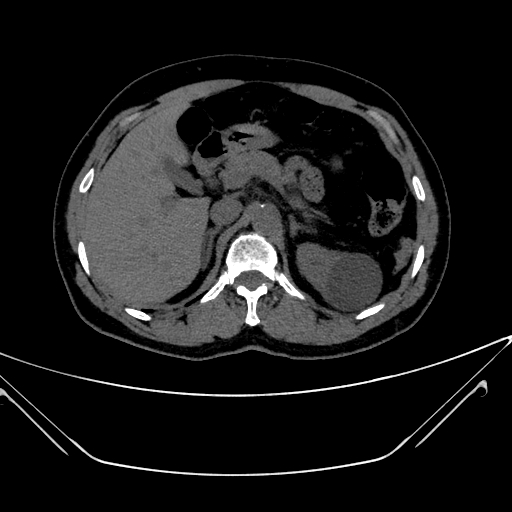

img

Tumor